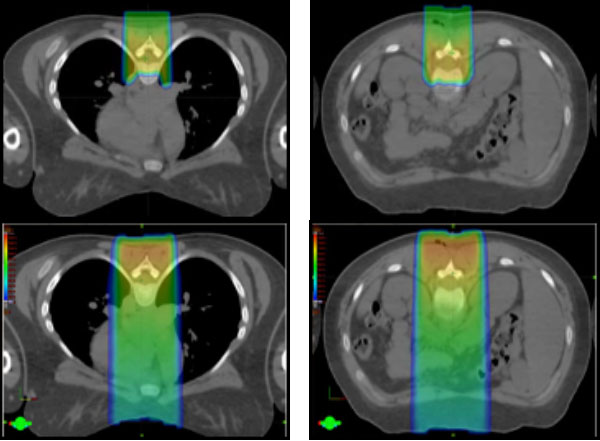

Medulloblastoma is one of the most common malignancies in children. It usually starts in the 4th ventricle region of the brain. However, it is a high-grade tumor that can use the fluid circulating in the nervous system to spread throughout the brain and spine. Although surgery is needed for diagnosis and symptom relief, the most important part of the treatment is radiation therapy, including radiation to the entire brain and spine. This treatment, called craniospinal irradiation (CSI), is usually given within a few weeks after surgery. In addition to the usual risks of treating the central nervous system mentioned above, spinal treatment with conventional radiation gives radiation to the lung, heart, thyroid, bowel, liver and kidneys, and gonads. Proton therapy significantly reduces radiation to the lungs and eliminates radiation to other organs. After CSI, additional radiation is given to the tumor itself or surgical bed in the fourth ventricle. The use of protons for this part of treatment will decrease the long-term intellectual, hormonal, and hearing effects by eliminating excess radiation to those sites.